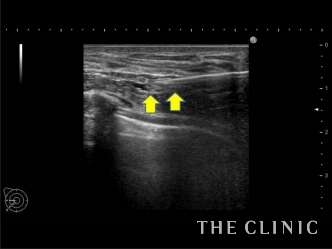

この方は施術を受けたクリニックでヒアルロン酸溶解の処置を受けられているのですが、まだ残っている気がするためエコー検査に来院されました。

実際に診てみると、確かにヒアルロン酸が残っていて、黒い塊として確認できました。

触診では困難なため、リアルタイムで映し出されるエコーの映像を確認しながら、ヒアルロン酸(しこり内)に確実に溶解液(ヒアルロニダーゼ)を注入します。

これにより、ヒアルロン酸の加水分解が始まり数十秒でジェル状に。それを吸引除去しました。

画像の矢印の少し上、真ん中から右端へ入っている白い線が先程の治療で使った吸引管ですが、ヒアルロン酸を除去したことにより、施術直後からしこりがなくなっていることが確認できます。